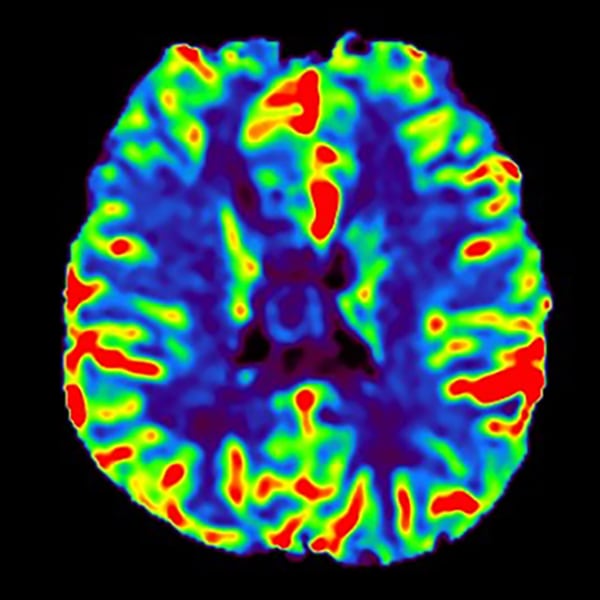

T1WI低信号、T2WI高信号、FLAIR高信号、DWIでやや高信号の腫瘤。Gdで腫瘤は造影されず、DSC-Perfusionでは辺縁~中心部に一部血流の高い部分あり。MRスペクトロスコピーではCho上昇とNAA低下がみられる。Low grade gliomaを疑う。後日、摘出手術が施行され、病理診断はoligodendroglioma NOS(Grade 2)であった。

当該疾患の診断における造影MRIの役割